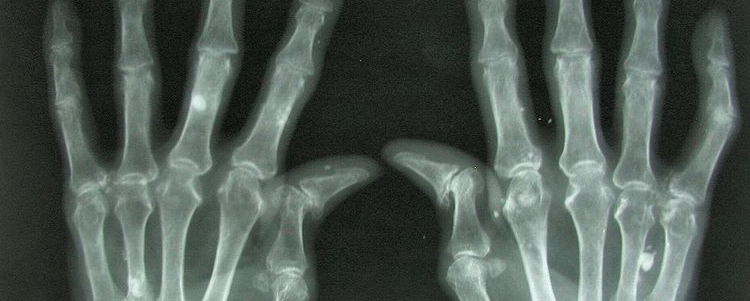

adherence

07/29/2020

Researchers recently asked patients with rheumatoid arthritis and their physicians about the biggest hurdles they face in controlling the disease. Take our poll to express your opinion on this issue.